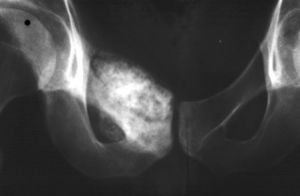

多發生於20~30歲,多見於股骨下端、脛骨上端,呈偏心性位於乾骺端或骨幹,皮質骨有擴張。其病理特徵為含有豐富的粘液樣或軟骨樣基質的梭形或星形細胞。手術切除植骨能治癒。(10)軟骨肉瘤,好發部位為軀幹骨,以骨盆為多見,亦可於四肢長管狀骨的近側。扁平骨的軟骨肉瘤多自中央開始後破壞皮質穿入軟組織。長管狀骨起自乾骺端,在髓腔內蔓延同時穿破鄰近皮質到軟組織,可出現Codman三角和不規則的放射狀骨針與骨肉瘤相似。軟骨肉瘤的組織學結構和生物行為是多變的,有生長緩慢分化好與生長迅速分化差兩種類型。分類

骨癌中骼骨,肋骨是惡性腫瘤常見轉移部位,大約占1/3,骨轉移中脊柱最常累及,其次肋骨、骨盆和長骨近端、胸骨和鎖骨。臨床上骨轉移常引起病人劇痛,廣泛性骨轉移可導致貧血和血小板減少。晚期破壞骨質,以致引起病理性骨折。